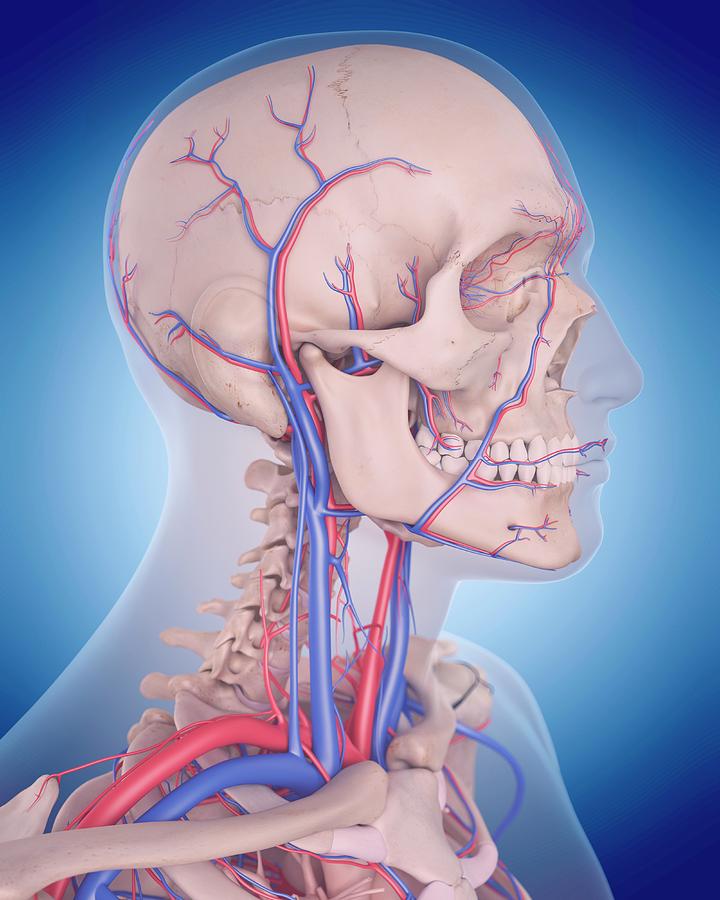

Анатомия внутренней яремной вены: КТ изображения